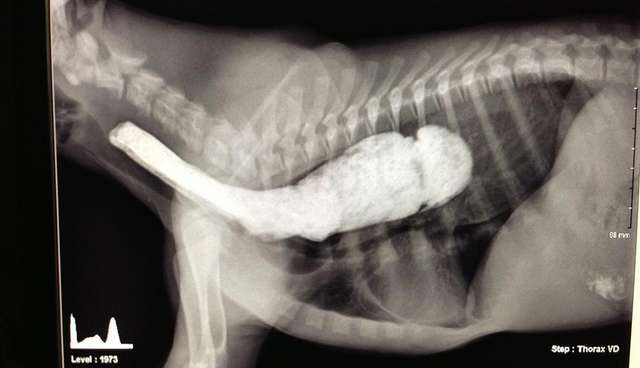

Most cases of megaesophagus can be diagnosed using thoracic radiography; Megaesophagus (me) is a condition in which there is enlargement and poor peristalsis of the esophagus. Megaesophagus in cats is uncommon. Megaesophagus in cats is either congenital (present since birth) or acquired. Megaesophagus in pets | petplan. Symptoms of megaesophagus in cats. Humans, dogs, cats (rarely), ferrets and other animals can suffer from this disease. Dilation of the esophagus results in difficulty swallowing.

Megaesophagus is a disorder of the esophagus characterized by diffuse dilation and decreased peristalsis.

Most cases of megaesophagus can be diagnosed using thoracic radiography; However, certain breeds are at risk for congenital me, meaning they are born with me. The vestibular system, located within the brain and middle and inner ear, is the disease can cause muscle weakness and difficulty exercising in norwegian forest cats. It is most often found in dogs, less frequently in cats and the least frequently in horses (broekman and kuiper 2002, morgan 2003, van geffer et al. Megaesophagus may be congenital or a problem secondary to other disorders. Megaesophagus (me) is a condition in which there is enlargement and poor peristalsis of the esophagus. Dilation of the esophagus results in difficulty swallowing. When swallowing, animals with megaesophagus are prone to accidentally inhale their meal because the reflex that prevents this.